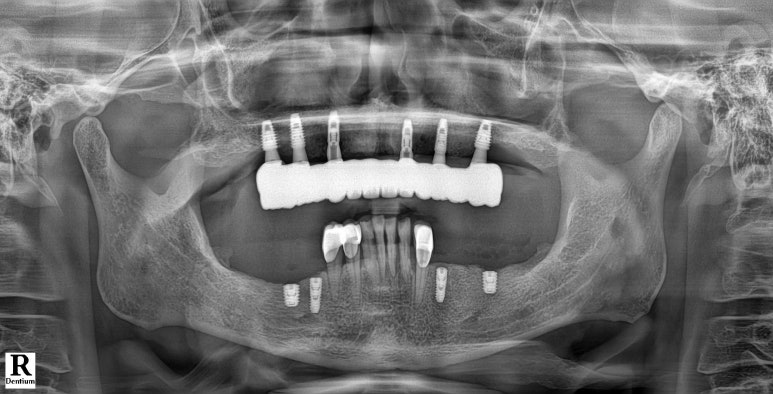

좌: 틀니를 착용하고 엑스레이를 찍은 모습, 우: 풀아치 임플란트를 식립한 직후 (2024년 7월 1일)

강남 풀아치 임플란트 (좌: 2024년 7월 1일, 우:2024년 9월 23일 완성)